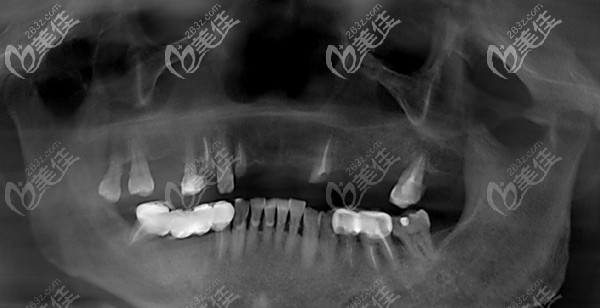

64岁阿姨口内检查:多颗牙缺失,深覆合深覆盖,12、14、22残根,牙体变红,13、15、17、27 II-III°松动,余牙缺失。

诊断结果:牙列缺损,牙周炎,牙体缺损

治疗方案:拔除上颌余牙,allon6即刻负重种植修复

王阿姨来到南京贝芽口腔,在护士的陪伴下,测量体温表登记,随后做了全景CT检查获取口腔数据。